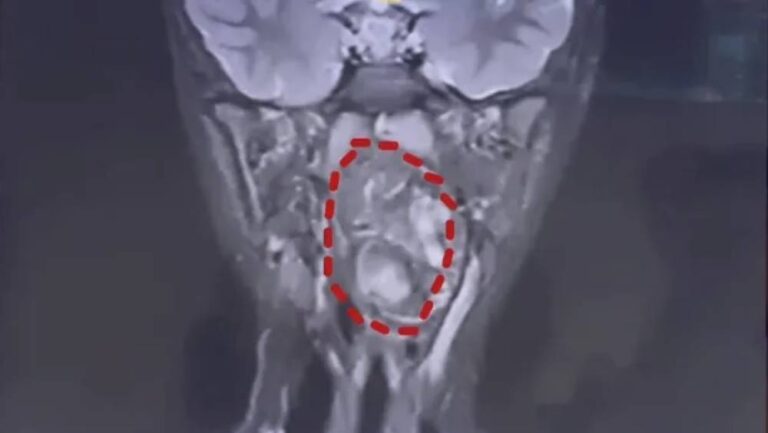

南京一名35歲王姓女職員因長期工作繁忙、飲食不定時,尤其忽略早餐,最終導致膽囊內形成大量結石。在一次…